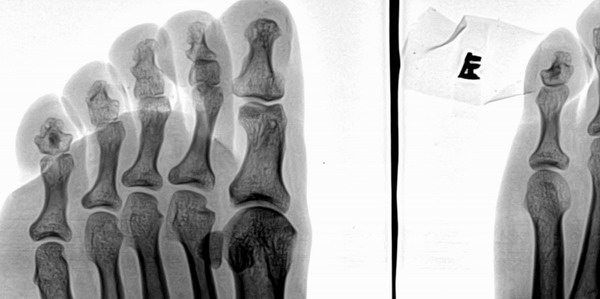

以下是引用浮华在2007-5-22 18:39:00的发言:[br]小趾中节趾骨高密度影,边界清,无明显骨质破坏--骨岛?

小趾中节趾骨高密度影,边界清,无明显骨质破坏--骨岛?

骨岛,姆趾近节关节下有个小囊装影。

小趾近趾节远端透亮纹是怎么回事啊,重迭就这么巧吗?